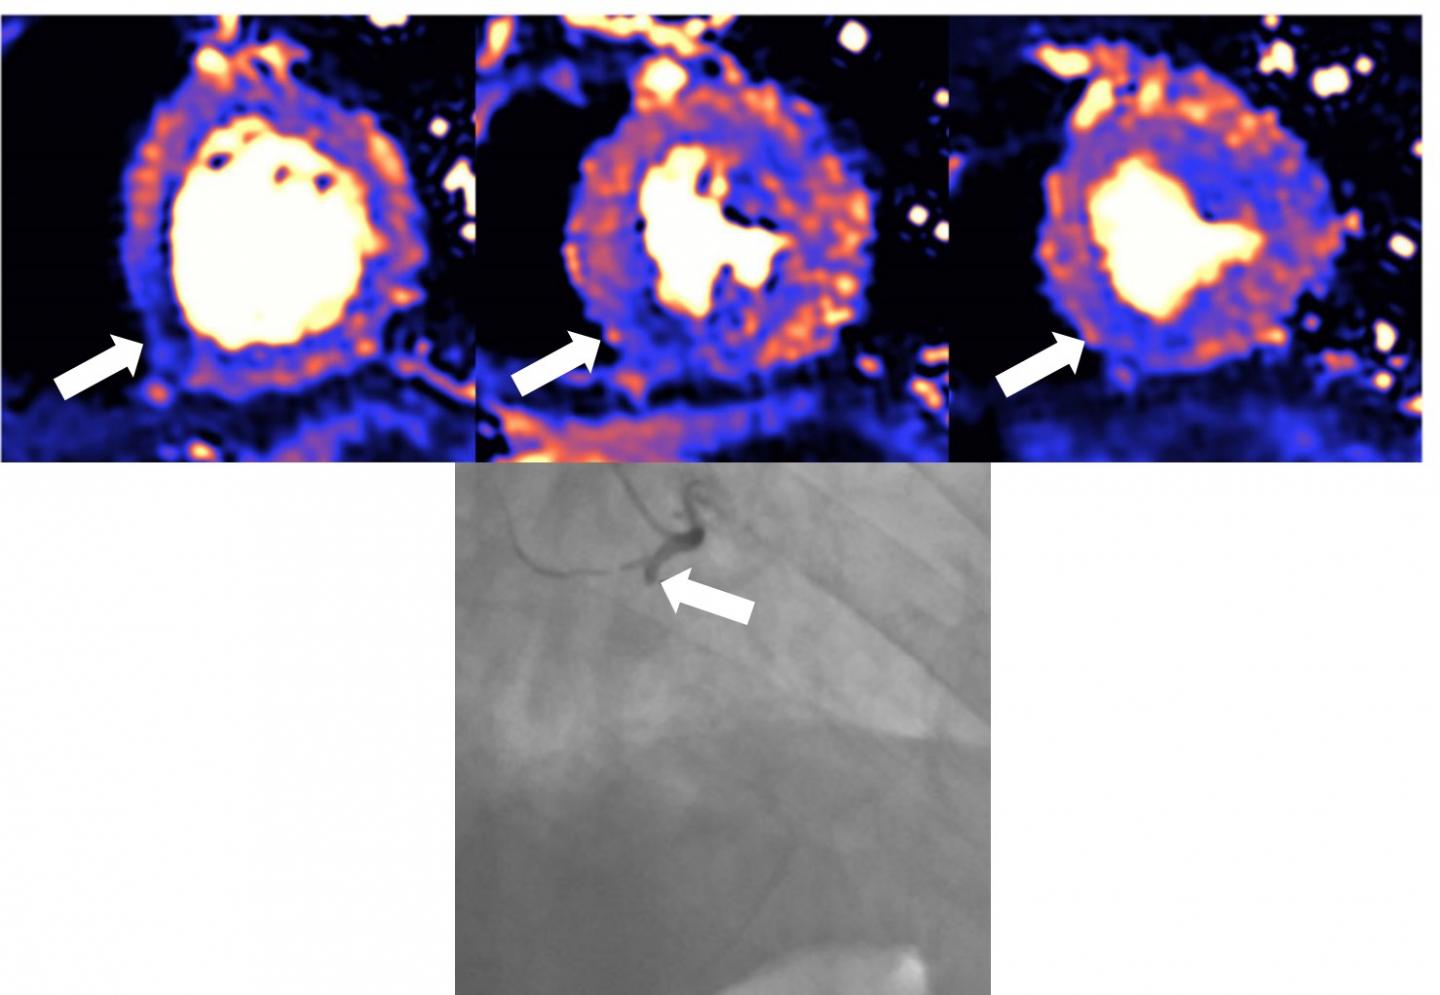

Around 50% of patients who have been hospitalised with severe COVID-19 and who show raised levels of a protein called troponin have damage to their hearts. The injury was detected by magnetic resonance imaging (MRI) scans at least a month after discharge, according to new findings published today (Thursday) in the European Heart Journal [1].

Damage includes inflammation of the heart muscle (myocarditis), scarring or death of heart tissue (infarction), restricted blood supply to the heart (ischaemia) and combinations of all three.

The function of the heart's left ventricle, the chamber that is responsible for pumping oxygenated blood to all parts of the body, was normal in 89% of the 148 patients but scarring or injury to the heart muscle was present in 80 patients (54%). The pattern of tissue scarring or injury originated from inflammation in 39 patients (26%), ischaemic heart disease, which includes infarction or ischaemia, in 32 patients (22%), or both in nine patients (6%). Twelve patients (8%) appeared to have ongoing heart inflammation.